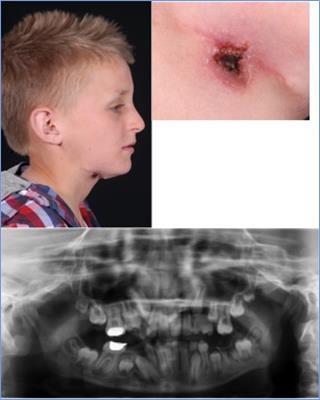

This was a referral made to the ENT department by a GP of a 12-year-old school boy who had a non healing wound in the right submandibular area. His GP and another ENT-Department had previously treated him for several months with topical antibiotic ointment and a surgical excision was also performed, however, the non healing area recurred shortly after the procedure.

On clinical examination, the lesion was 1cm in diameter and was located in the submandibular region on the right side. A 2.5 cm scar after attempted excision of the skin lesion was noted. A thorough history revealed, from the patient and his parents, multiple dental problems and treatments in the past (Figure 3 a-b). The patient was then referred to our department.

Figure 3a-c.Skin lesion right submental area, OPG mixed dentition with moderately restored LR6 and UR6, a big cavity around the LL6 and periapical radiolucany around LR6

Skin lesion right submental area, OPG  mixed dentition with moderately restored LR6 and UR6, a big cavity around the LL6 and periapical radiolucany around LR6

The performed OPG showed a mixed dentition with moderately restored LR6 and UR6, a big cavity around the LL6 and periapical radiolucany around LR6 (Figure 3c). We performed a dental extraction of the LR6 and a punch biopsy of the lesion. The microbiological and histological results were similar to the first two cases described and shortly after the procedure the wound healed well with no recurring problems or lesions reported.